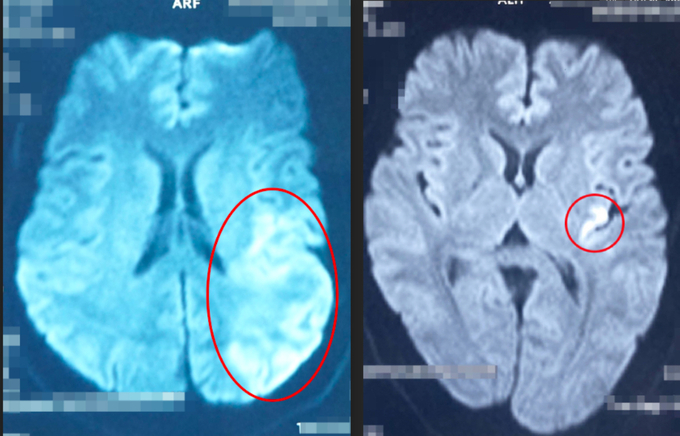

Người phụ nữ 43 tuổi trong lúc gội đầu cho khách ở tiệm cắt tóc. Bất ngờ bà có các triệu chứng bị đột quỵ. Nhanh chóng người phụ nữ được đưa vào bệnh viện cấp cứu.

Bệnh nhân được đưa vào Bệnh viện Đa khoa Xuyên Á Vĩnh Long ngày 11/5 sau một giờ khởi phát triệu chứng. Hình ảnh chụp CT xác định bệnh nhân bị nhồi máu não cấp bán cầu trái giờ thứ nhất, bác sĩ chỉ định dùng thuốc tiêu sợi huyết (rTPA).

Sau can thiệp, bệnh nhân hồi phục nhanh chóng, mạch máu bị tắc đã được tái thông hoàn toàn. Người phụ nữ nói chuyện rõ lời, sức cơ bên liệt hồi phục hoàn toàn, có thể đứng, đi lại và sinh hoạt gần như bình thường. Hiện, bà đang được tiếp tục theo dõi sức khỏe và điều trị nguyên nhân, dự phòng tái phát.